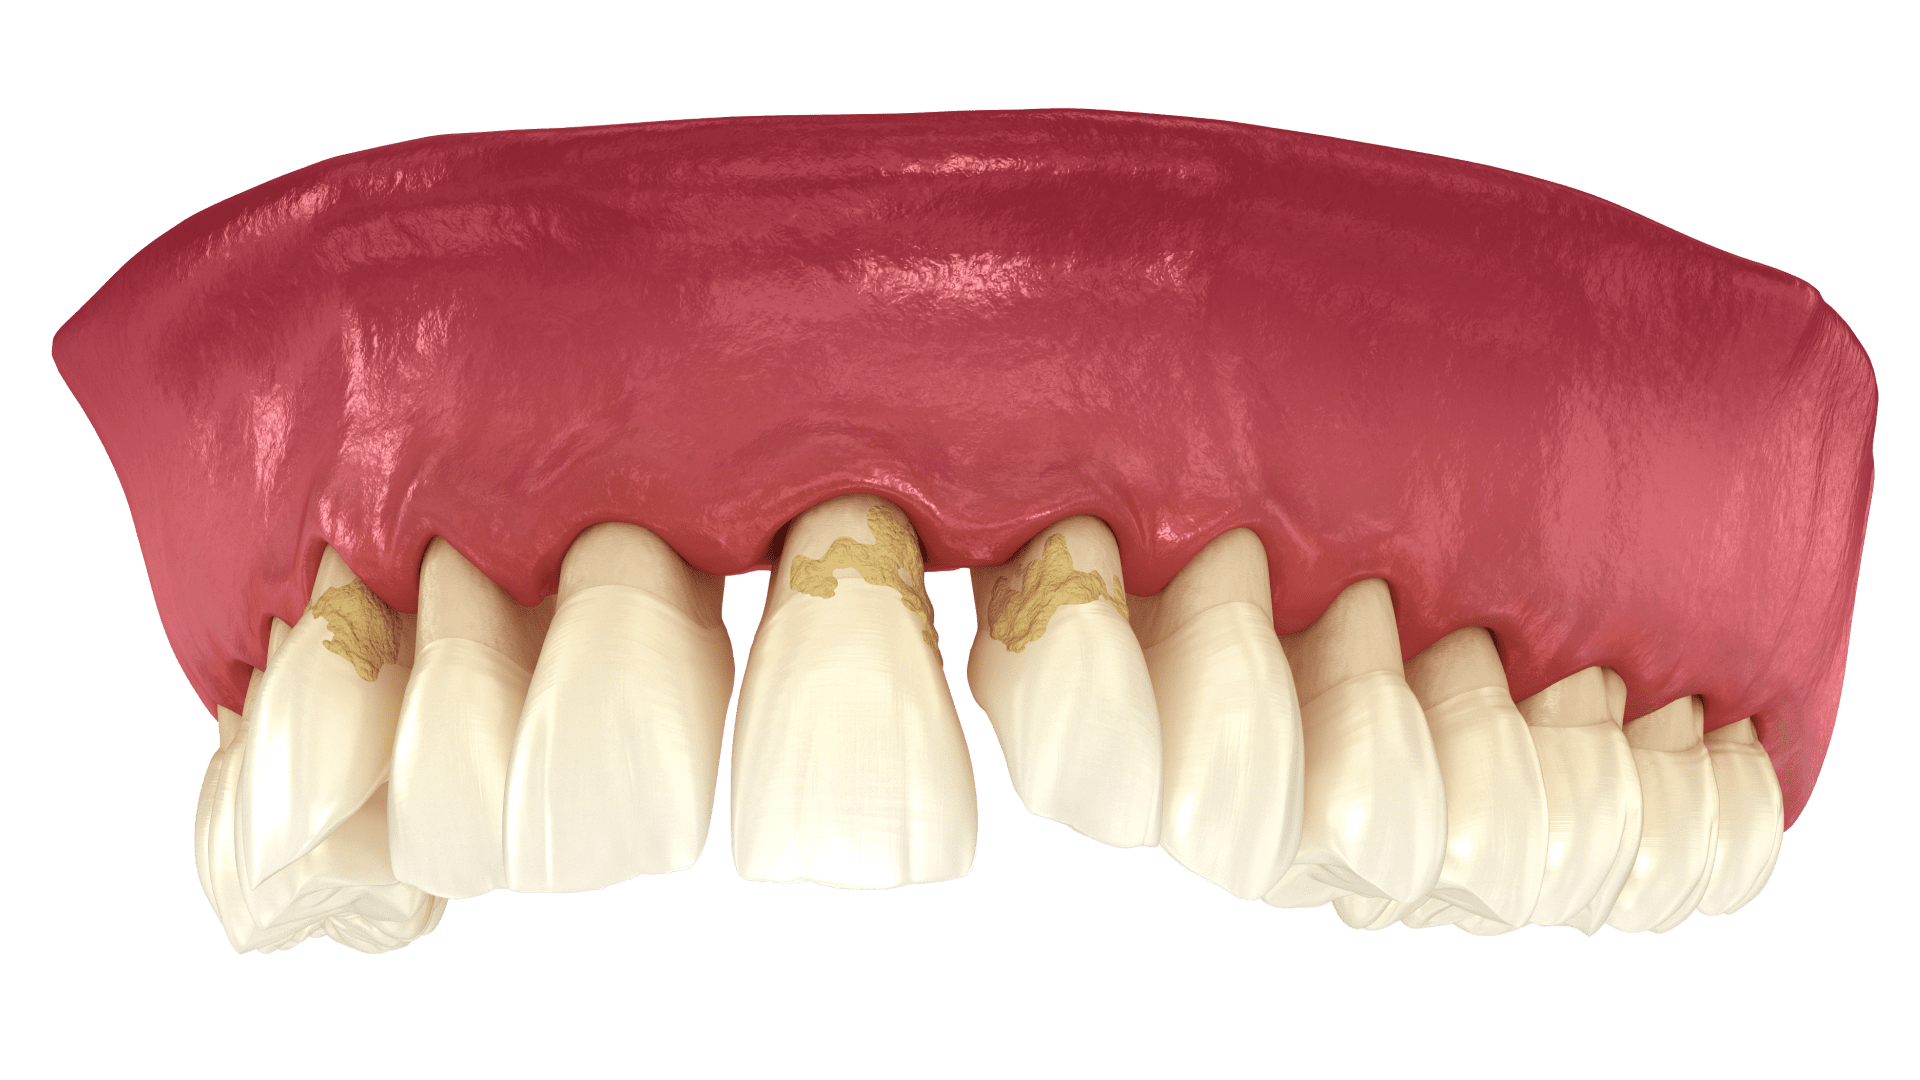

Кровоточивість, набряк, почервоніння ясен і неприємний запах з рота — це перші симптоми захворювань пародонту, які не можна ігнорувати. Без своєчасного лікування запалення призводить до руйнування опорних тканин зуба, його рухливості та, зрештою, втрати. Щоб запобігти серйозним ускладненням, варто звернутися до лікаря вже на початковій стадії, а не чекати переходу хвороби у гостру форму.

Ясна — це важлива опорна структура, яка утримує зуби та захищає їх від інфекцій. Їх запалення — це сигнал про початок захворювань пародонта. Якщо його ігнорувати, воно може перейти у пародонтит — хронічне ураження тканин і кістки, що призводить до рухливості та втрати зубів.

Здорові ясна мають світло-рожевий колір і щільно прилягають до шийки зубів, не оголюючи кореневі частини. Лікування ясен необхідне при поверхневому та глибокому ураженні тканин пародонту, в які проникають різні бактерії та наліт, провокуючи розвиток захворювань.

Гінгівіт — це запалення ясен у ділянці одного або кількох зубів. Найчастіше уражається край ясен або тканини між зубами. Хвороба зачіпає лише слизову оболонку й не поширюється на кісткову тканину, тому вважається менш небезпечною, ніж інші пародонтальні захворювання. Проте без лікування гінгівіт може перейти у пародонтит.

Основна причина розвитку — зубний наліт, у якому накопичуються бактерії. Вони виділяють токсини, які надалі провокують розвиток захворювання. В результаті формується бактеріальна бляшка, яка руйнує тканини пародонту.

Пародонтит

Пародонтит — це запальне захворювання ясен, при якому уражується опорний апарат зубів, зокрема ділянка з’єднання зубних одиниць з кісткою щелепи. При прогресуванні запалення ясна відходять від зубів, утворюючи пародонтальні кишені. У ці простори потрапляють залишки їжі, що створює сприятливі умови для розмноження бактерій та утворення гною.

Пародонтоз — це хронічне неінфекційне захворювання, яке вражає всі тканини пародонта, а саме ясна, кістку альвеолярного відростка, зв’язки та цемент зубів. Пародонт відповідає за фіксацію та утримання зубних одиниць у правильному положенні під час жування. При пародонтозі ця функція порушується, і без своєчасного лікування ризик втрати зубів значно зростає.